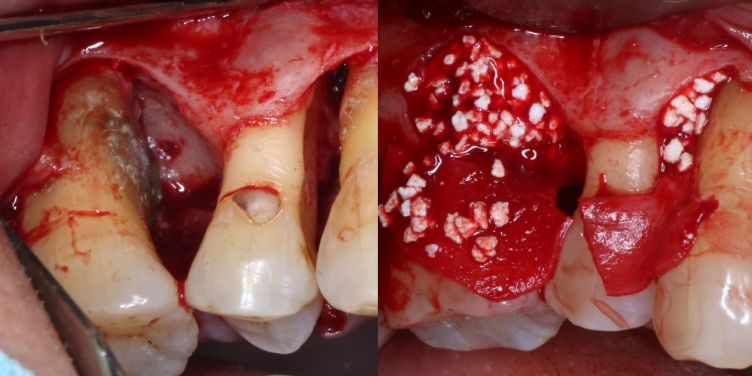

抜歯と言われても残せる可能性があります

「他院で断られても諦めないでください」

他院で断られても諦めないでください

昨今では重度歯周病に対する治療の研究が進み、現在では歯周病により溶けた歯槽骨の再生が可能となっています。根の先端を超えるような骨吸収が起きていたとしても残すことができるとの報告もあります。

当院には、保存不可と診断された歯を保存してきた多数の実績があります。

難易度の高い治療ではありますが、歯科用CTによる正確な診断、マイクロスコープを用いた精密な治療により可能となります。

従来の歯周病治療とは異なり、組織が歯根面に到達することをメンブレン(人工膜)で防ぐことにより、歯根膜をもととした組織/細胞の新生を伴う結合組織性付着を形成できるようにする方法です。

歯周病によって歯を支える歯槽骨が溶けてしまっている場合などに、メンブレン(人工膜)を挿入しておくことで歯ぐきの侵入を防ぎつつ歯周組織の再生するスペースを確保できます。

歯周組織再生療法

まず、歯を支える骨(歯槽骨)が大きく失われている場合には、「歯周組織再生療法」を行います。

これは、特殊なたんぱく質製剤(エムドゲイン®など)や人工骨を用いて、溶けてしまった骨や歯周組織を再生させる先進的な治療法です。

失われた組織を“再び取り戻す”ことで、歯の動揺を抑え、長期的に安定した口腔環境を築くことが可能になります。 -

フラップ手術

(歯肉剥離掻爬術)また、炎症が歯ぐきの深部まで進行している場合は、「フラップ手術(歯肉剥離掻爬術)」を実施します。

歯ぐきを丁寧に開いて奥深くの歯石や感染組織を直接確認しながら取り除く方法で、マイクロスコープを併用することで精密かつ低侵襲な処置が可能です。